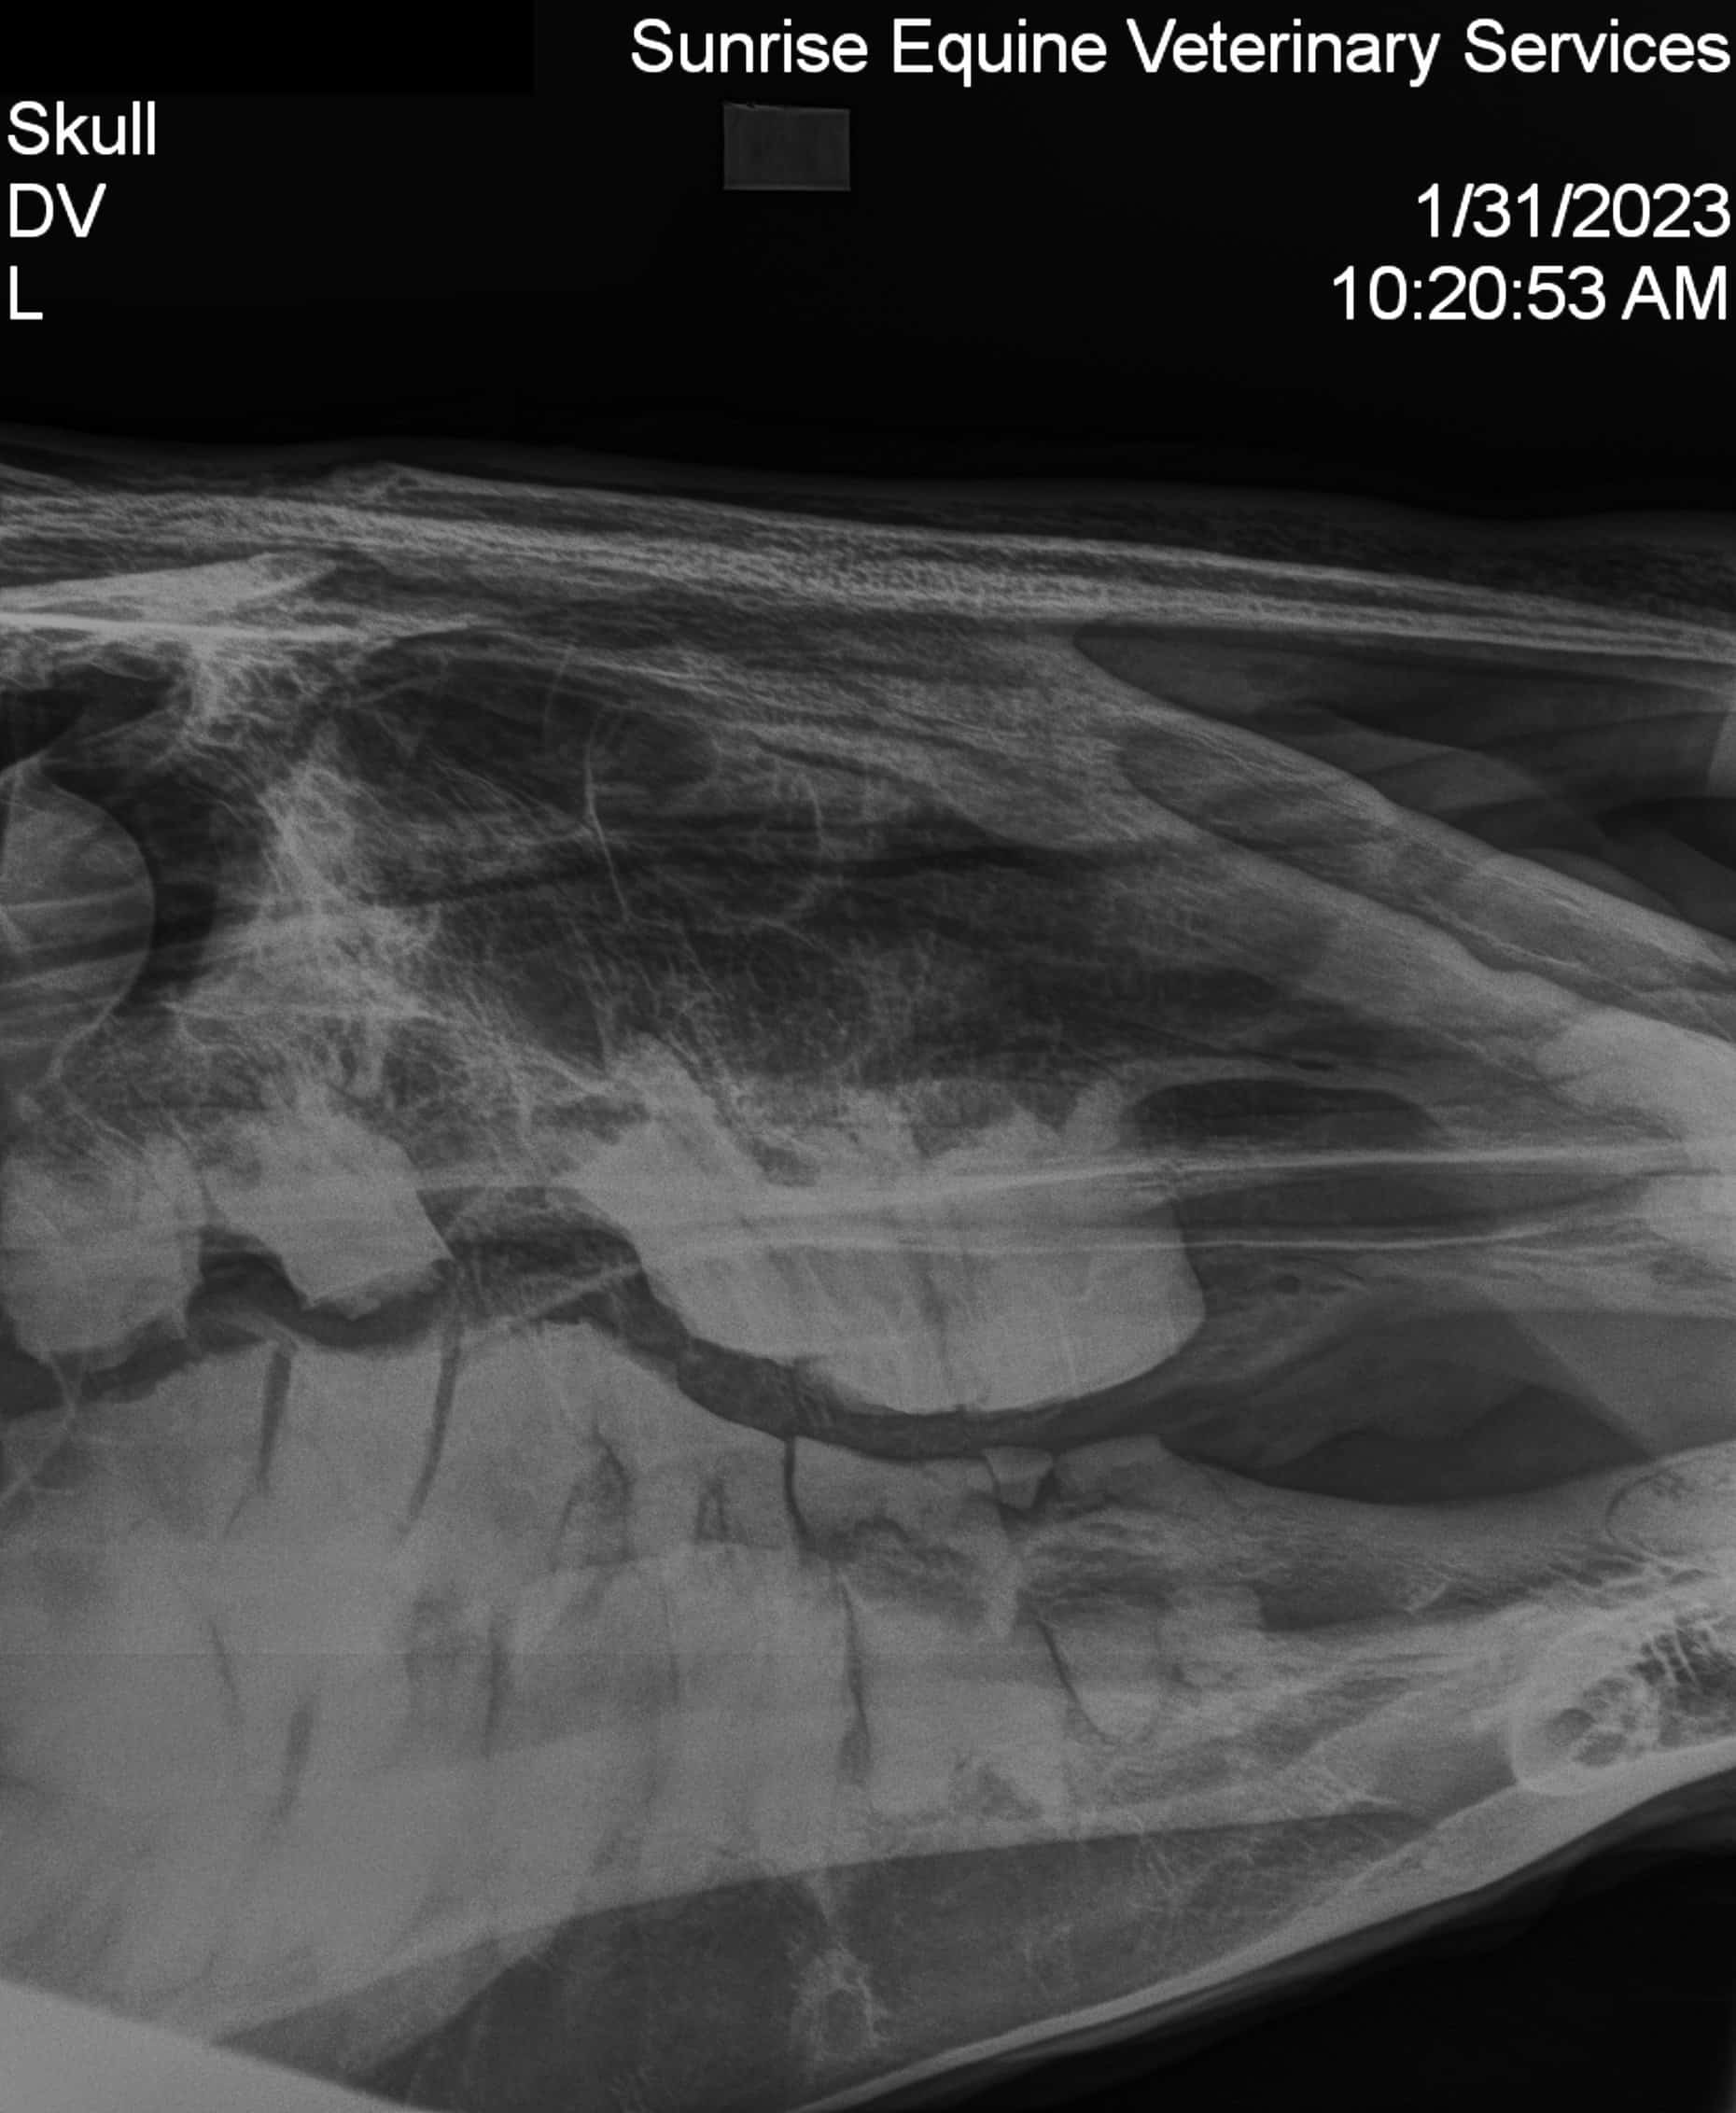

After entering the pasture to throw hay, a volunteer spotted one of our furry team members with blood on their nose. Moving closer and upon further inspection, their nose and surrounding eye socket appeared to be swollen and tender with touch. They gently guided him towards the barn and into his stall to examine a little closer, grateful for the shelter and warmth during the process. He showed us, without words, that he was uncomfortable, his eyes seeming to say, “Something’s wrong, I need your help.” We listened to him and heard his need, calling our good friends at Sunrise Equine for their expertise. There’s a saying I’ve heard of when you have to call the vet that goes “only one of you gets to panic and it’s never your turn.” We spent time speaking comforting words to our pal and ourselves while we waited. Our incredible veterinary team arrived shortly thereafter with Dr. Delaney confirming our furry team member was right and that something was indeed wrong. After many x-rays and examinations it was discovered that our friend had a facial fracture and would need to be separated from his herd in order to spend time healing and recovering without further injury risk. The team moved deftly into action, one team member clearing snow from a space with a bobcat and ensuring proper fencing for a safe recovery area, another spending time with our furry teammate while he recovered from sedation medication, and yet another devising a nutrition plan to feed him while being wary of his pain and limited movement.